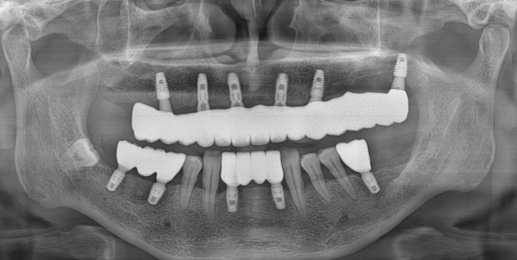

임플란트는 단순히 심는 것이 아니라, 뼈와 잇몸 상태에 맞는 정확한 위치와 각도가 중요합니다. 그래서 수술하는 의사의 실력이 중요하죠. 이 때 잘못 심는다면 아무리 관리를 잘해도 임플란트 수명은 5년 미만으로 떨어집니다. 또한, 임플란트의 품질·제조사에 따라서도 장기 안정성이 달라지는데요. 이 부분은 다음 칼럼에서 자세히 다뤄보도록 하겠습니다.

정밀 CT와 3D 시뮬레이션으로 뼈 상태를 분석하고, 최소 절개로 수술 부담을 줄입니다.